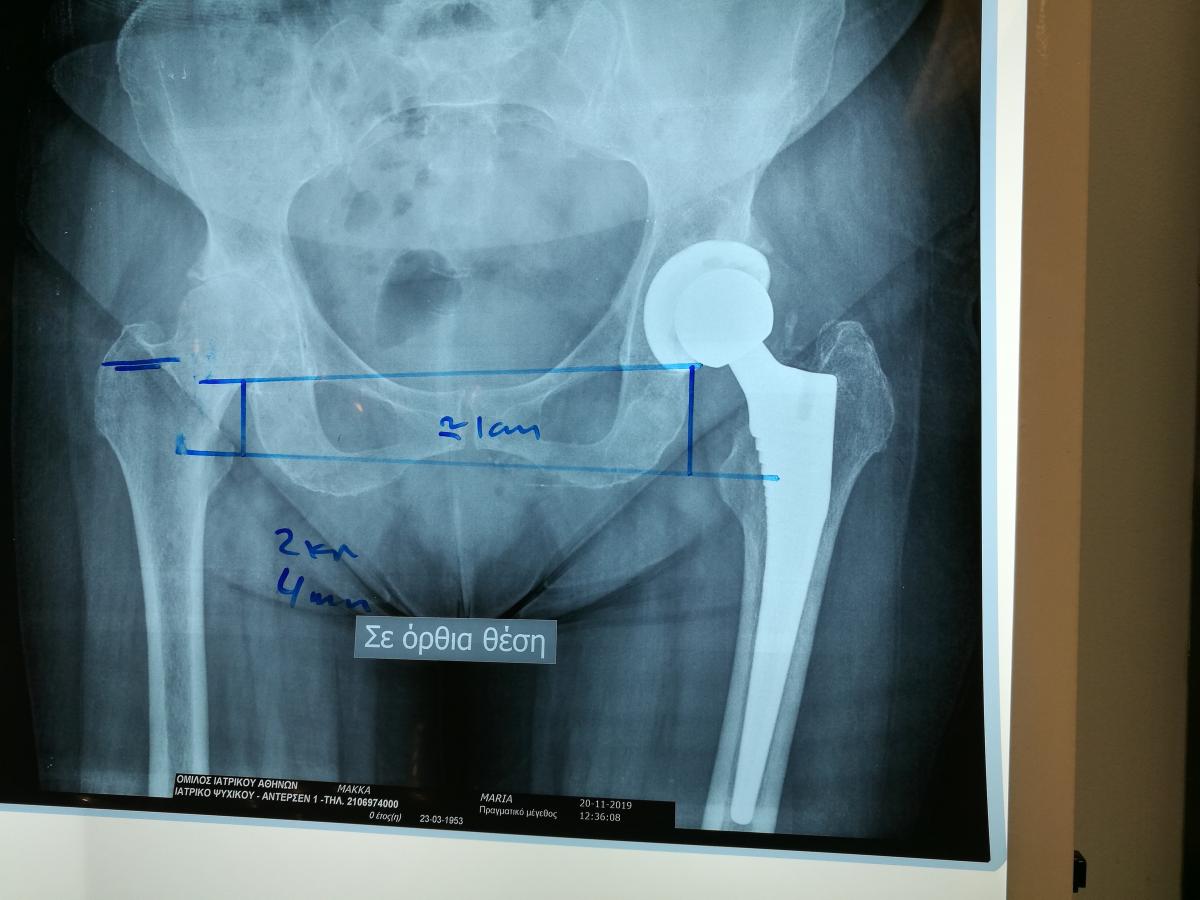

Компанія Lima надала стажування в ортопедичній приватній клініці місті Афіни Греція в листопаді 2019 року. Ендопротезування кульшового суглоба протезами компанії Lima малоінвазивним передньо-латеральний доступом у професора Христодулоса.